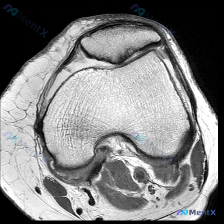

这是一张提供的单张膝关节矢状位MRI影像,用户核心疑问是:影像中是否存在软骨异常?

- 序列与定位:这张影像骨髓呈高信号,软组织对比度高,骨皮质为低信号,结构显示清晰,更倾向是T1加权或质子密度(PD)序列,不是纯T2加权序列,切面为标准膝关节矢状位,能清晰看到髌骨、股骨远端、胫骨平台、前后交叉韧带和半月板结构。

- 骨性结构与骨髓:股骨远端、胫骨平台、髌骨轮廓完整,没有骨皮质中断,骨髓信号也没有异常的高低信号区

- 关节软骨:股骨髁和胫骨平台的关节软骨轮廓完整,信号没有明显异常增高或缺失

- 半月板:整体是均匀低信号,没有异常高信号延伸到关节面,形态也没有异常

- 交叉韧带:前交叉韧带走行自然,连续性好,信号均匀;后交叉韧带呈典型弓形低信号,走行连续,没有信号异常

- 关节腔与周围软组织:没有明显异常积液,髌腱、股四头肌腱连续,髌下脂肪垫信号均匀,腘窝也没有明确囊性占位

针对用户提出的「软骨异常」疑问,这张影像上没有发现明确的软骨异常信号或结构改变,整张单张影像也没有发现膝关节内部明确的损伤或病理改变。